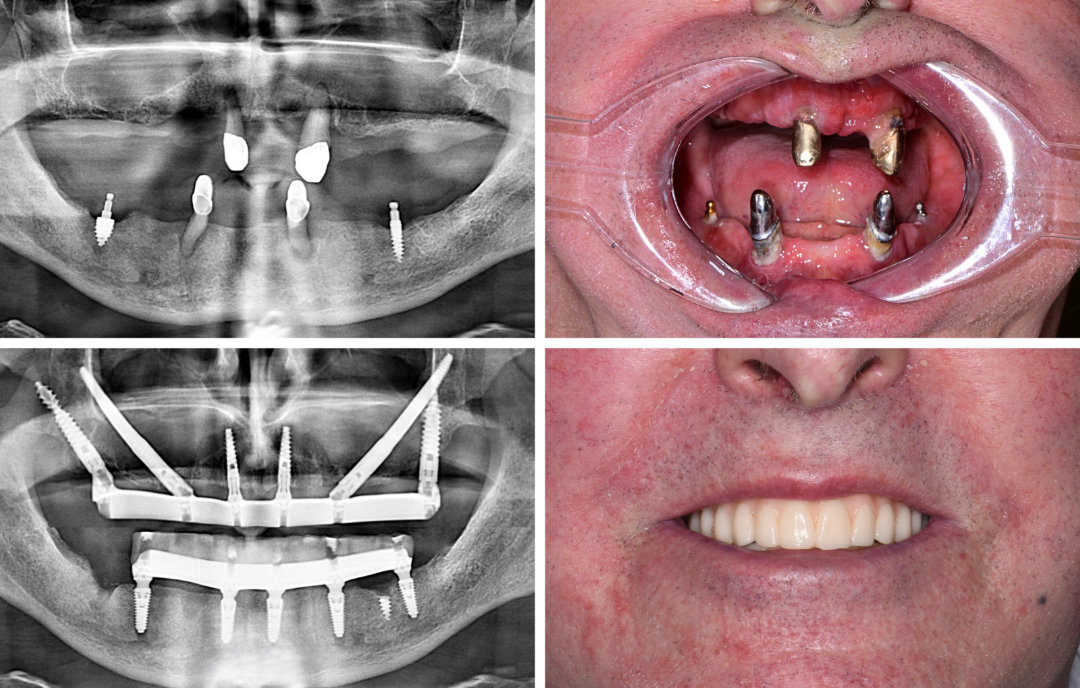

Ausgangssituation

Eine 64-jährige Patientin war viele Jahre auf der Suche nach einer festsitzenden, implantatgetragenen Lösung. Doch niemand konnte ihr eine passende Therapie anbieten.

Lösung

In ITN: Navigierte Rekonstruktion des Ober- und Unterkiefers mit Quad-Zygoma- und Pterygoid-Implantaten im Oberkiefer sowie 5 herkömmlichen Implantaten im Unterkiefer. Sofortige provisorische Brücke in beiden Kiefern – in nur einer Operation.

Vorteile

Eine vermeintlich austherapierte Patientin erhielt die gewünschte Implantatlösung – innerhalb kürzester Zeit und in beiden Kiefern. Eine Full-Arch-Rekonstruktion kann bei guter Planung in einer einzigen Sitzung erfolgen.